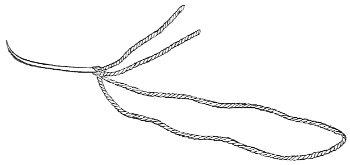

Silver wire and silkworm gut are the best sutures in the operation of perineorrhaphy.

The suture is conveniently attached to the needle by means of a silk carrier (Fig. 31).

Fig. 31.—Perineal needle with silk carrier.

Fig. 32.—Shot-compressor.

The sutures may be fastened by passing the ends through a perforated shot which is slipped down to the line of union and compressed by the shot-compressor (Fig. 32). All blood should be carefully removed from the surfaces that are brought together. The sutures should only be sufficiently tense to produce accurate apposition. A light gauze drain should be introduced in the vagina, and should be removed in forty-eight hours. Afterward one vaginal douche of about a quart of warm bichloride solution (1:2000) should be administered every day. After the douche the labia should be separated and the vagina carefully dried by cotton held in dressing-forceps. Except in those cases in which the sphincter ani is involved, the bowels may be moved on the second or third day. The woman should stay in bed for two weeks, at the end of which time the sutures should be removed. 67 She should avoid heavy lifting, long standing, and bicycle- or horseback-riding for two months after the operation. Constipation should always be avoided. Coitus may be resumed six weeks after operation.